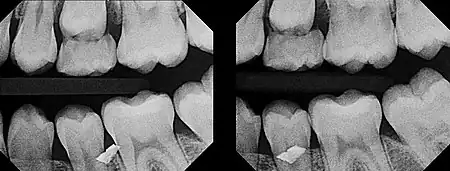

The initial radiograph (left) indicated that a metal foreign object was embedded somewhere in or near the teeth, but upon clinical examination, it could not be found anywhere in the gum tissue. Upon taking another radiograph (right) exposed at a very severe distal angulation, however, the metal fragment appeared to move a great deal to superimpose on the facial aspect of the premolar, indicating that the fragment was way more buccal than initially suspected. With the use of this second film, it was determined that the metal fragment was indeed embedded in the cheek.

Diagrammatic representation of the buccal object rule being employed. In the first radiograph (left), the objects appear on the film in almost the same relationship that they share in reality. But by shifting the x-ray collimator (radiation source) to one side and tilting it towards the objects (right), the objects appear on the film in a distorted relationship. The object closer to the x-ray collimator (generally the buccal object) will appear to reposition itself on the film at a greater distance than the object farther from the collimator (generally the lingual object) and it will appear to shift on the film in the direction of the beam.